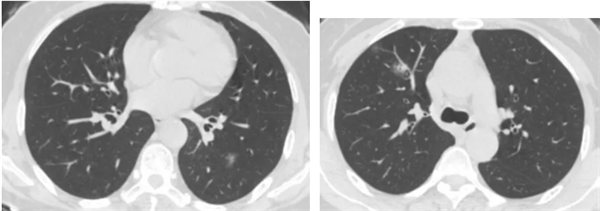

患者王先生今年58歲,近期間斷咳嗽20余天不見好轉,常常是陣發性干咳,晚上癥狀加劇夜不能寐,無其他顯著異常體征。在我院呼吸與危重癥醫學一科住院后,主管醫生安排檢查胸部CT,結果顯示:右上肺及左下肺多發斑片狀滲出,境界不清伴暈征。經主診組魏勝全主任醫師分析:患者是一位中老年男性,結合病史、影像學表現為磨玻璃結節,伴暈征,感染性病灶考慮非典型病原菌,考慮有感染支原體、結核、真菌的可能,需要進一步完善呼吸道病原學檢測、結核T細胞檢測、GM、G試驗等相關檢查來協助診治。

科主任王惠霞主任醫師指示:影像學考慮肺部感染明確存在,相關炎性指標均未見明顯異常,患者有干燥綜合征病史,長期服用免疫抑制劑、影像學表現為磨玻璃結節、大小不等,形態相似,伴暈征,結核T細胞檢測陰性,暫可排除肺結核。真菌D葡聚糖檢陽性,提示真菌性感染(是曲霉?念珠菌?還是隱球菌?)同時要和肺腺癌等鑒別,進一步支氣管鏡檢查及新型隱球菌莢膜抗原檢測。在王惠霞指導下安排患者進行了支氣管鏡檢查及新型隱球菌莢膜抗原檢測,最終檢查結果顯示,新型隱球菌莢膜抗原陽性,明確為新型隱球菌肺炎。